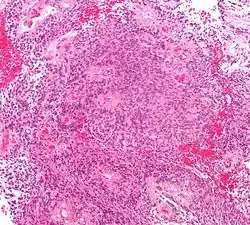

-

Micrograph of a myxopapillary ependymoma. HPS stain. -

About 10% of ependymomas are benign myxopapillary ependymoma (MPE).[8] MPE is a localized and slow-growing low-grade tumor, which originates almost exclusively from the lumbosacral nervous tissue of young patients.[8] On the other hand, it is the most common tumor of the lumbosacral canal comprising about 90% of all tumoral lesions in this region.[9]